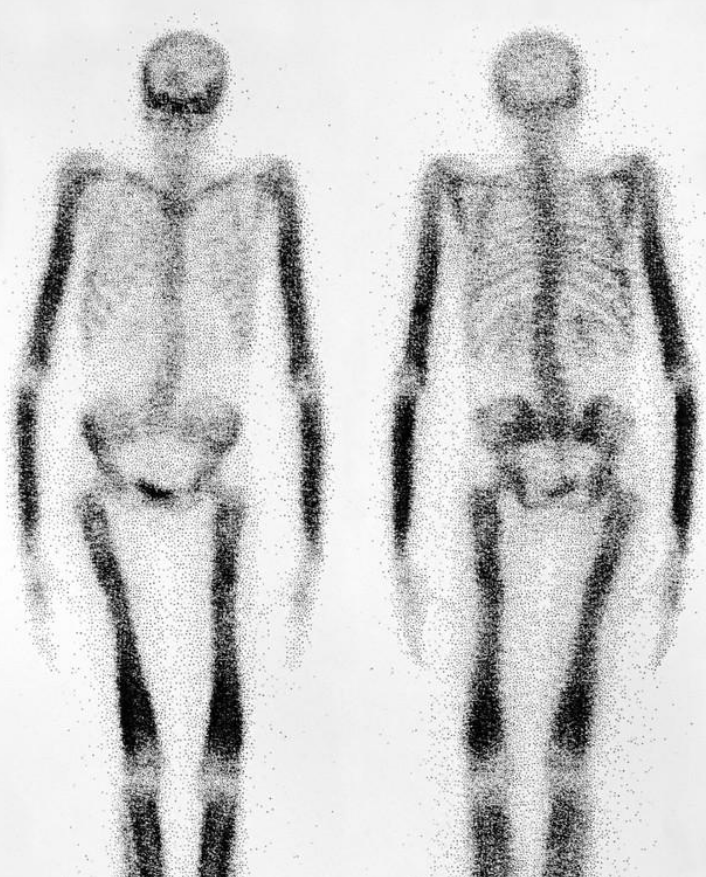

骨扫描:主要表现为转移病灶核素摄取增加

总结:ECT可以作为初筛检查,X线、CT可以明确骨质破坏的程度,MRI有助于了解骨转移对周围组织的影响尤其是脊柱稳定性的情况!